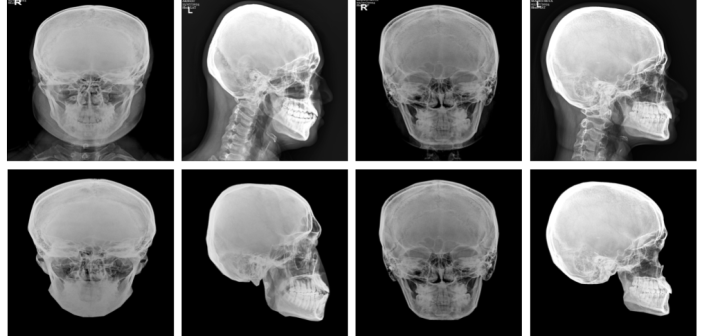

Refer to caption

Figure 2: Sample image of X-ray dataset used, where soft tissue eliminated images are shown down to their respective raw images.

Our study was conducted on the S2F [prasad2025fcrinvestigatinggenerativeai] dataset which contains 51 X-ray scans with their respective face pair image from voluntary persons, aged between 21-30 years as shown in Figure 2. Specifically, 22 females and 29 male volunteers are there in this dataset. More precisely, for training YOLO pose models, this dataset contains 102 skull–face pairs, which consist of 51 lateral views and 51 frontal views. We divided the dataset into training, validation, and testing sets using a 70:20:10 ratio. Specifically, 10 pairs were subject wise randomly selected for testing, 21 for validation, and 71 for training.

An X-ray image of the face also contains information about soft tissues, and to make the X-ray image resemble the skull image precisely, we eliminate the soft tissue part. Soft tissue elimination (STE) enables the training of a YOLO-pose [yolo_pose_v8, yolo_v11] model more precisely for skull images. This operation was applied to all the images in S2F dataset to isolate skeletal structures and facial contours. We manually outline soft tissue areas on each skull image using Roboflow’s tools, specifically designed for segmentation to distinguish between soft tissue and bone. Figure 2 shows some samples of images before and after elimination of soft tissues. [For more details on soft tissue elimination, please refer to supplementary.]